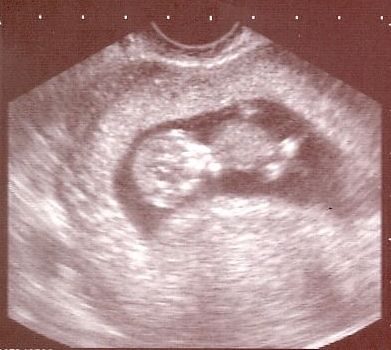

Én pénteken voltam dokinál, ma vagyok 8 hetes 1 napos, a babóval minden rendben, 16 mm-es, és már láttam, ahogy dobog a pici szíve. Nekem végülis kiderült, hogy mitől volt vérzésem, polipom nőtt (ami a doki szerint a terhesség alatt normális), és abból jött a vérzés. Tehát minden rendben van, a magnéziumot is elhagyhatom. Marad az Elevit.